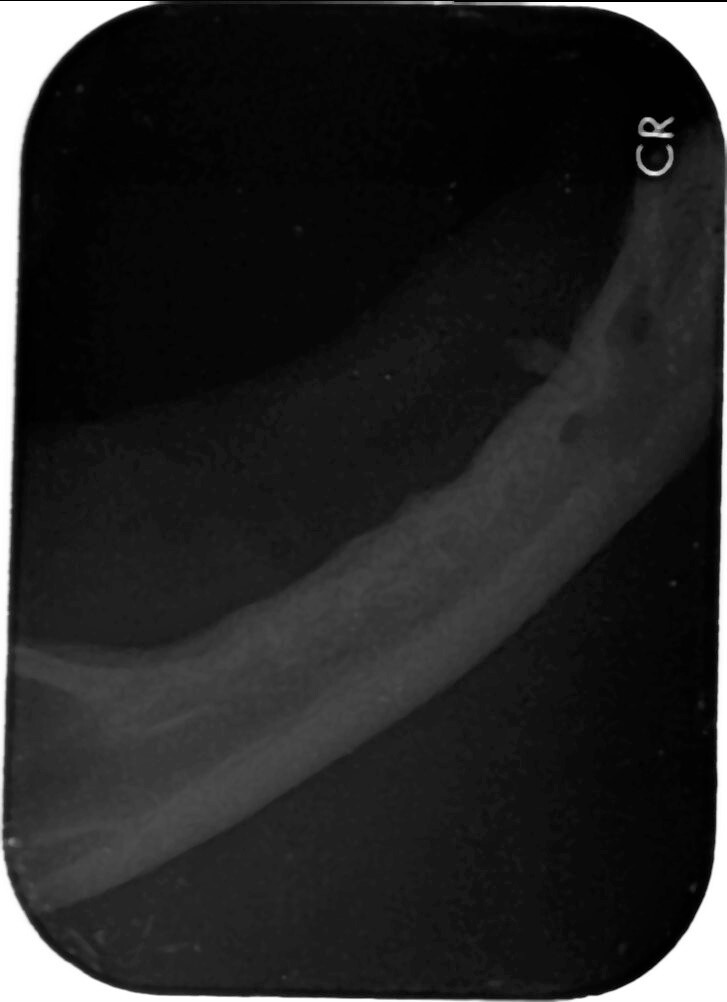

於他家醫院建議拍攝齒科x光 懷疑齒根殘存

10/5門診時 口內檢查可摸到雙側下顎有殘存齒根

狀況尚可 先開藥物 安排至維康動物院進行齒科x光

10/18維康麻醉進行齒科x光

及殘存齒根拔除

只發現下顎雙側各一齒根(如同門診可觸摸處)

本筆醫藥費用即為盈盈於維康進行齒科X光及殘存齒根拔除的費用